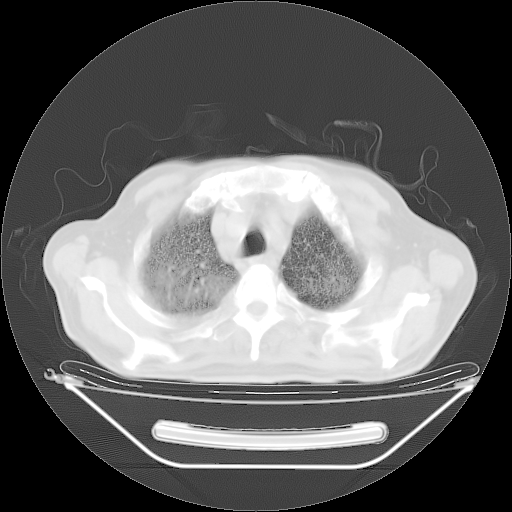

胸腹部CT,诊断意见:左上肺叶钙化灶、左侧胸膜局限性增厚并钙化、胆囊炎。描述部分肺组织呈磨玻璃样改变。